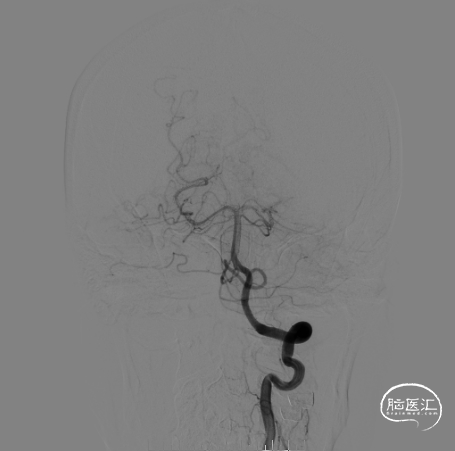

右侧颈总造影:右侧大脑中动脉瘤

畅医达(Accessway)0.017支架微导管在0.014微导丝引导下顺利到达右侧大脑中动脉M2远端,经支架微导管引入畅医达(Choydar)血流导向装置,3mm*15mm,推送平顺,然后跨瘤颈缓慢释放支架,支架头端打开良好。

支架部分释放后复查造影示支架位置良好,缓慢完全释放支架,支架打开良好,复查造影示支架位置良好,完全覆盖瘤颈,贴壁佳,瘤囊内可见造影剂滞留明显,OKM分级A3。

术后即刻正侧位造影显示载瘤动脉及远端分支显影无异常,瘤囊内可见明显造影剂滞留;Xper-CT未见出血。